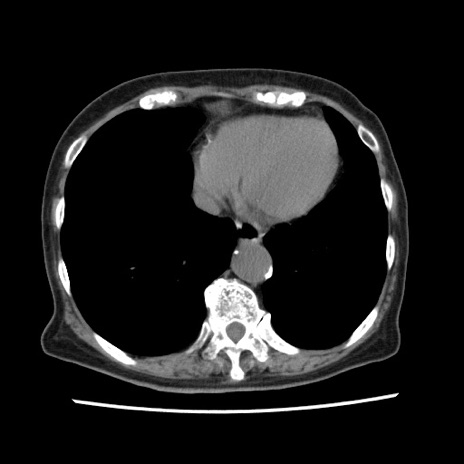

冠状断像

【症例】80歳代女性

【主訴】腹痛

【現病歴】8時間前から腹痛あり来院。

【既往歴】糖尿病、脂質異常症、子宮体癌にて子宮全摘術

【身体所見】意識清明・会話良好だが腹痛で苦悶様、全腹部にわたって反跳痛と圧痛あり

【データ】WBC 13600、CRP 0.14、LDH 224、CK 90